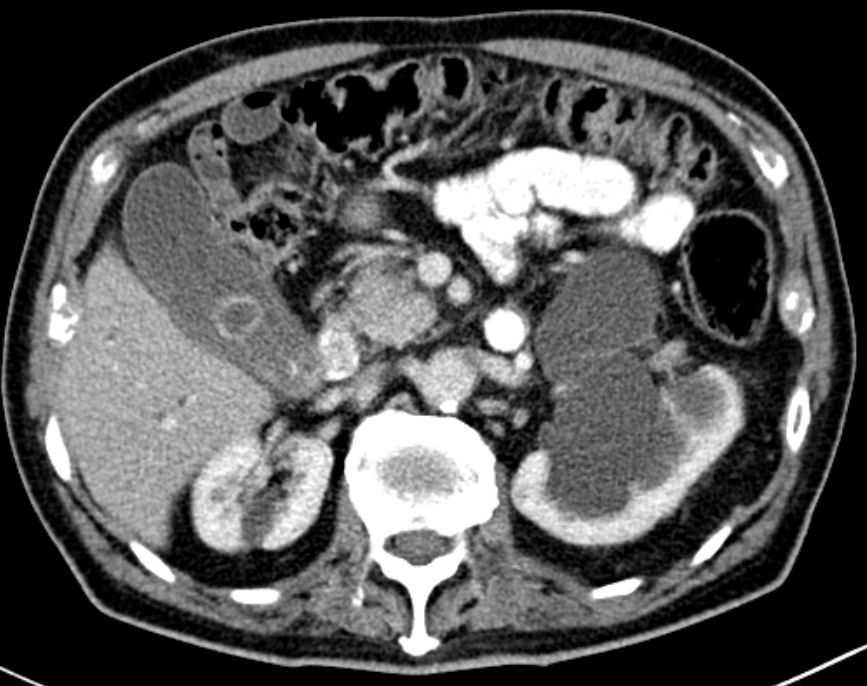

| Differential-Diagnose | Wichtigste Differential-Diagnose ist die chronische Pankreatitis. | 77-jähriger Patient mit 8kg Gewichtsabnahme sowie

intra- und extrahepatischer Cholestase. Verdacht auf einen Tumor im Bereich

des Pankreaskopfes. Nebenbefund: Harnstauung links durch Ureterabgangsstenose.

Das CT zeigt erweiterte intrahepatische Gallengänge.![]() |

Das CT zeigt eine erweiterte Gallenblase mit

Stein. Prominenter Pankreaskopf. Nierenstau links.![]() | ||||||||||||